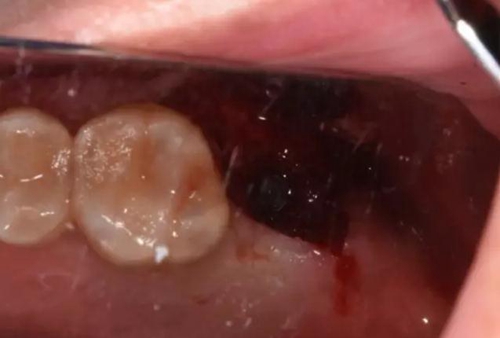

二期手術(shù)術(shù)中照